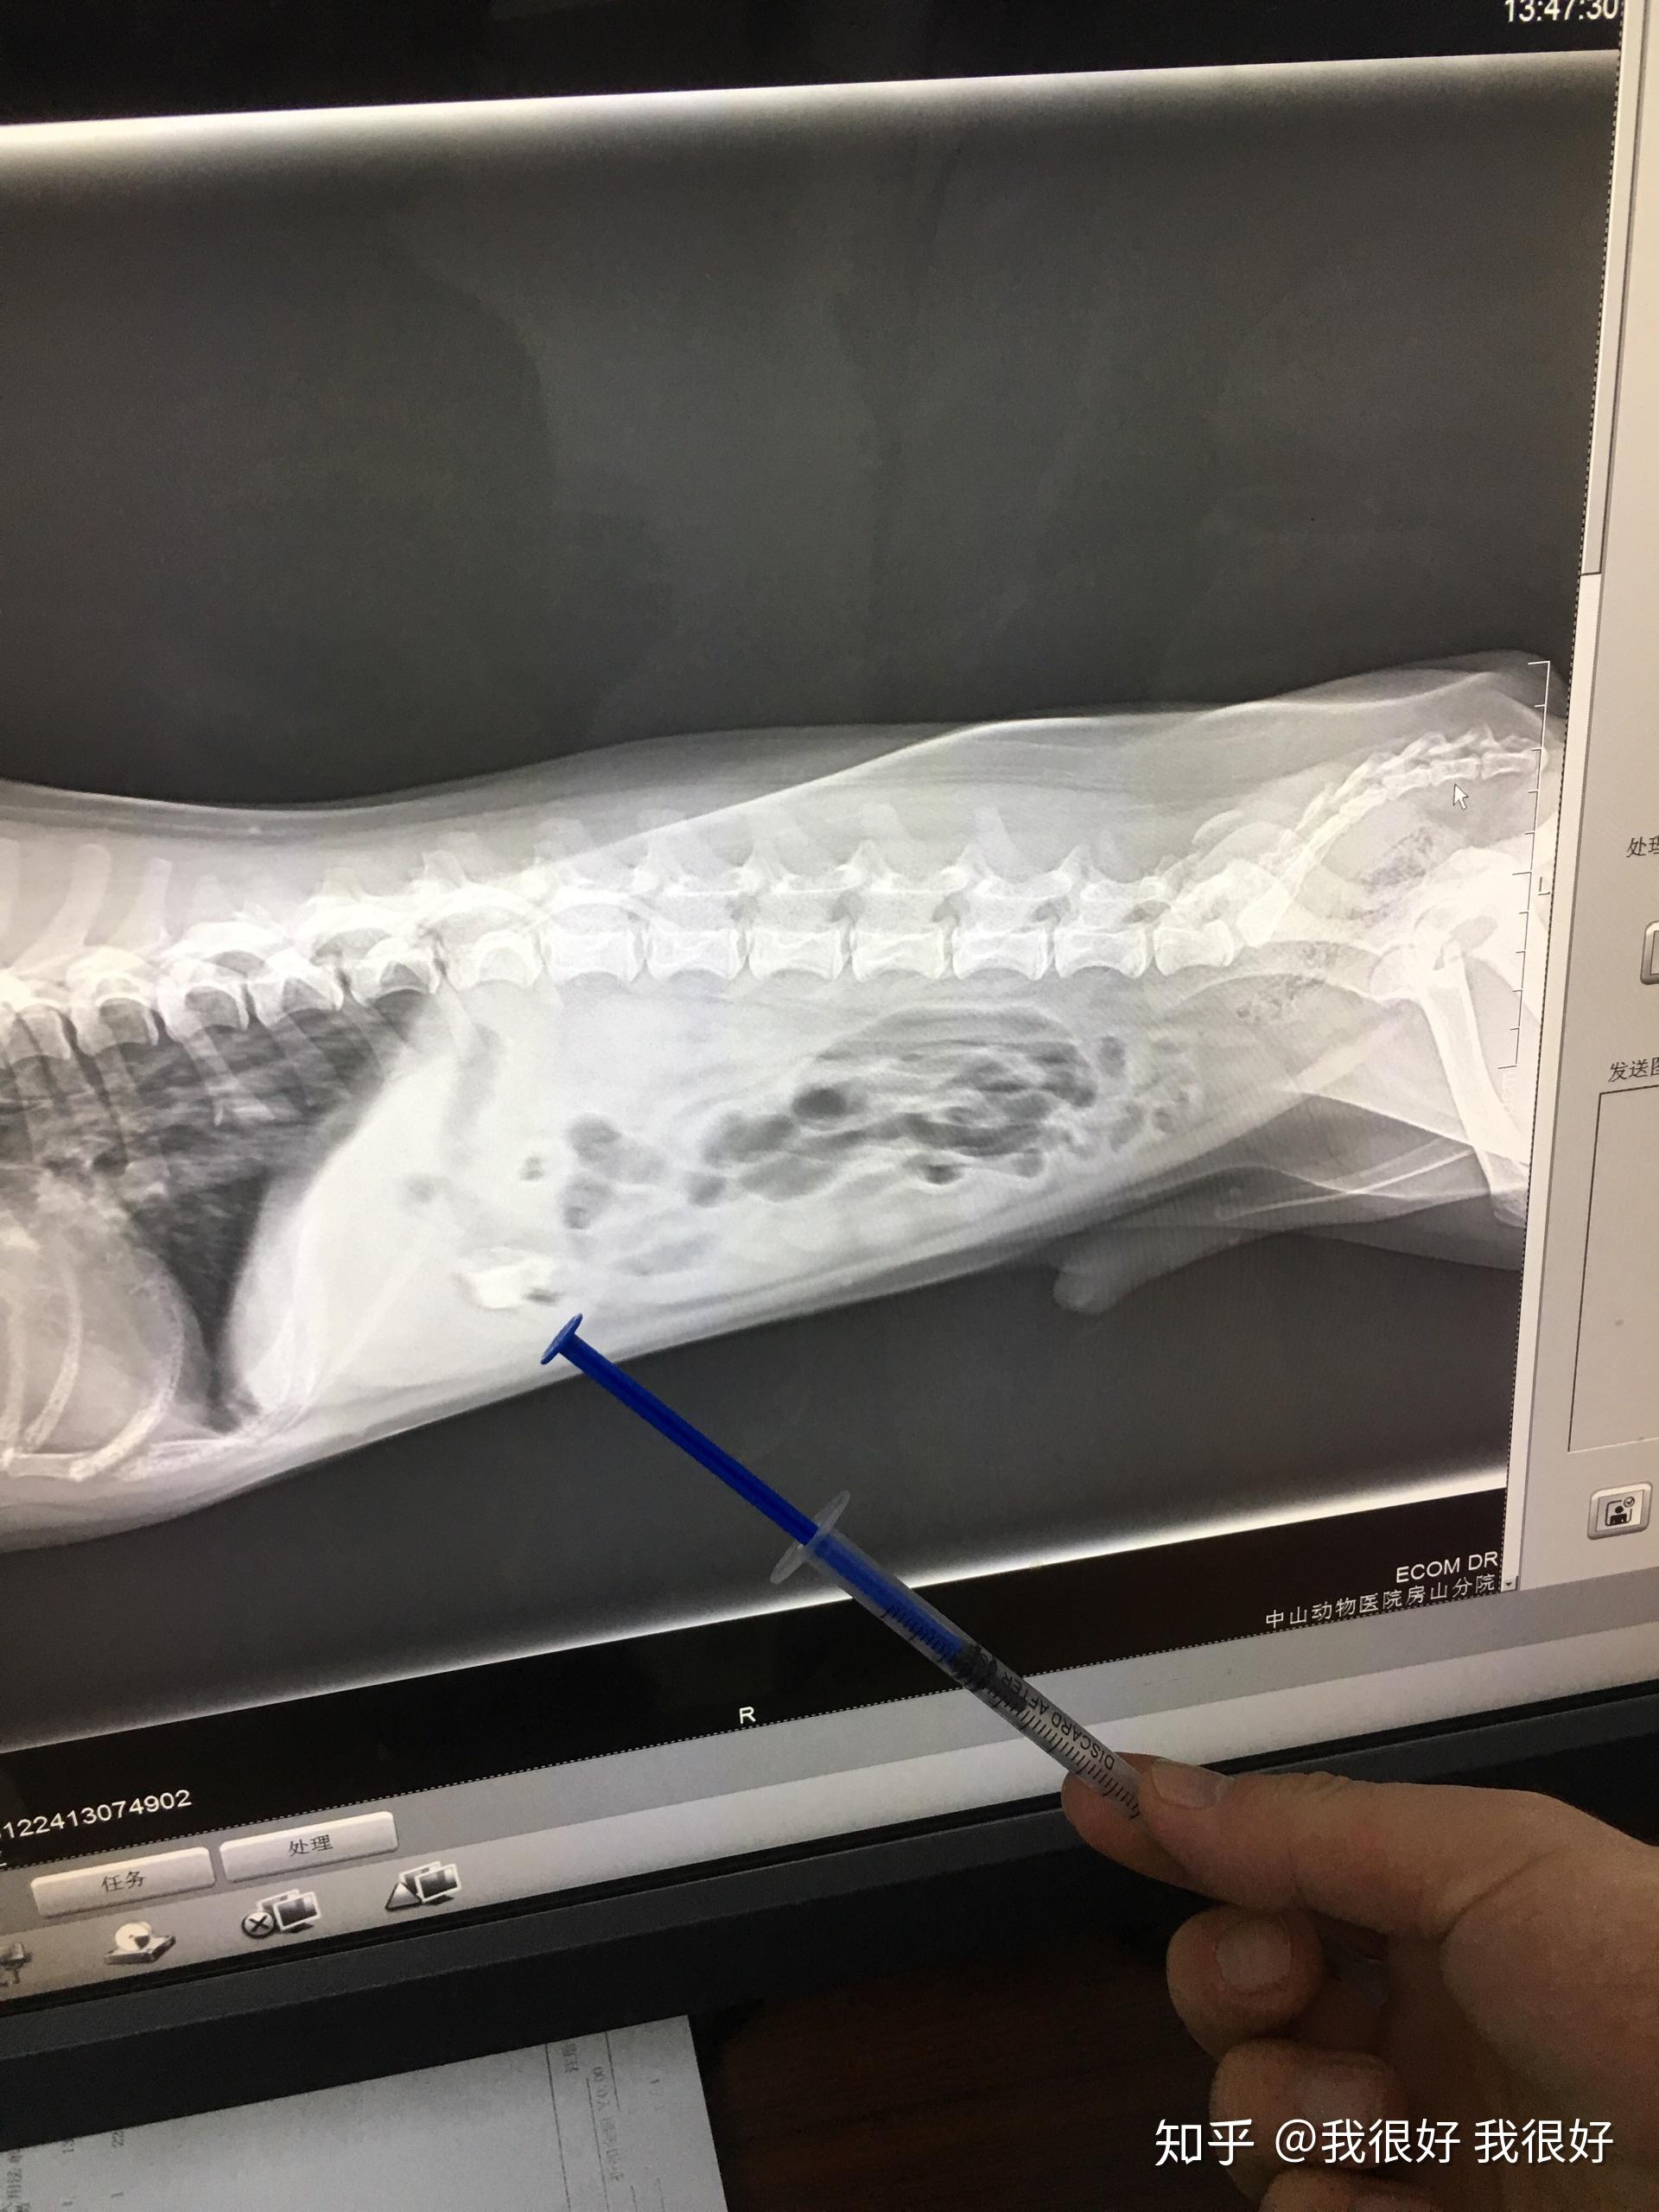

铲屎官狗子股骨胯骨到底有没问题

图片尺寸1440x1920